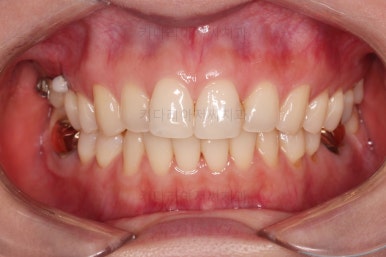

치료 종료시의 모습인데요.

임플란트가 잘 들어갔고 아래 앞니도 원하는 모습으로 잘 배열이 되었습니다.

부산치아교정비용 전후 비교해 볼게요.

치료기간은 임플란트의 안정성 때문에 길어지긴 했으나 사실상 내원횟수는 그리 많지 않으셨고, 교정장치가 눈에 보이는 기간은 7개월정도 밖에 안되었기 때문에 크게 문제되지는 않았던 것 같습니다.

여러 가지가 다 잘 마무리 되었습니다.